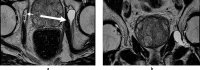

Objective: Acetabular paralabral cysts are common and are almost always associated with labral tears. Uncommonly, they extend into the periacetabular soft tissues or may propagate along peripheral nerves causing pain and hip dysfunction. The aim was to evaluate the clinical and MRI presentations of such cases including perineural propagation.

Results: 14 cases were recorded. The mean age was 56.9 years (range = 30-79 years) and female:male ratio was 1:2.6. The commonest presenting complaint was hip pain (10/14, 71.4%). Other complaints included groin pain, perineal pain and hip dysfunction. No symptoms were attributed to the acetabular paralabral cyst in 3/14 patients (21.4%). None had foot drop. The cysts were multilocular in all cases and were homogenously T2 hyperintense in 13/14 (92.9%). Labral tears were identified in 11/14 cases (78.6%). The sciatic nerve was most commonly involved in 5/14 cases (35.7%) with the obturator, medial femoral cutaneous nerve, femoral nerve, superior and inferior gluteal nerves also affected.No intervention was undertaken in 9/14 cases (64.3%). 5/14 (35.7%) underwent image guided aspiration and corticosteroid injection. 4/5 such patients reported reduced pain following the procedure.